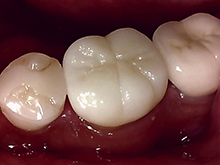

オールセラミックス

金属を使わずに全てセラミックを使用し、光の透過性を上げる事により自然な白い歯に回復させる方法です。

現在では土台から白い材質(ファイバーポストなど)の物を使用することにより、さらに透明感が増し天然歯に近似しています。

オールセラミックは近年進化を遂げており、強度や接着性がかなり改善され、審美的にとても優れたものと成って来ております。

オールセラミックにも色んな種類がありますが、当院ではe-max(二ケイ酸リチウムガラスセラミック、)ジルコニアセラミックスを採用しています。